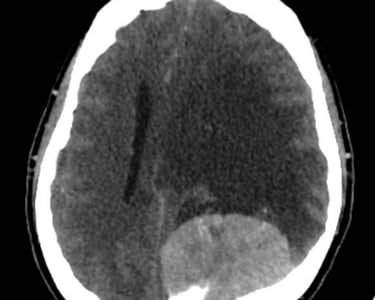

Hemorragias cerebrales

Traumatismos craneoencefálicos